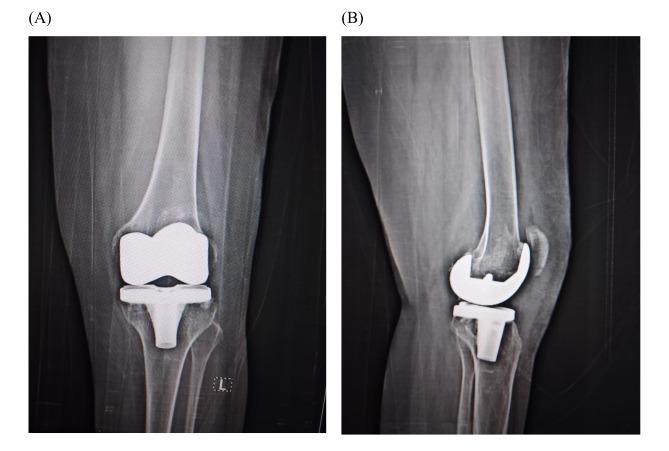

Von Willebrand disease (vWD) and hemophilia present unique challenges in orthopedic surgery due to their inherent bleeding risks and potential complications. While joint bleedings are well-documented in hemophilia, they are less understood in vWD, especially regarding their impact on daily activities and the development of arthropathy. We present a case of a young female patient aged 25 years with vWD Type 3 who underwent bilateral total knee replacement (TKR) due to end-stage knee osteoarthritis. Following two previous operations of the right knee at the age of 14, the patient had high degree of extra-articular valgus and intra-articular deformity, ankylosed knee in 30 flexion, osteopenia, and chronic patellar dislocation. Bilateral TKR was performed using patient-specific templating (PST) technology, which includes preoperative planning using a CT scan followed by surgical execution. Financial constraints and limited prosthetic resources necessitated a sequential approach to TKR, addressing the more affected right knee first. Despite many challenges, successful outcomes were achieved, with significant improvements in pain, mobility, overall satisfaction, and no complications at two-year follow-up. Our case highlights the importance of individualized treatment strategies, meticulous surgical planning, and postoperative care in managing knee arthropathy patients with bleeding disorders.

血管性血友病(vWD)和血友病在骨科手术中带来了独特的挑战,因为它们存在固有的出血风险和潜在并发症。虽然血友病患者的关节出血已有充分记录,但vWD患者的关节出血情况了解较少,尤其是其对日常活动和关节病发展的影响。我们报告一例25岁的3型vWD年轻女性患者,因终末期膝关节骨关节炎接受了双侧全膝关节置换术(TKR)。该患者14岁时右膝曾接受过两次手术,存在高度的关节外外翻和关节内畸形,膝关节在30度屈曲时强直,骨质减少,以及慢性髌骨脱位。双侧TKR采用患者特异性模板(PST)技术进行,该技术包括术前使用CT扫描进行规划,然后进行手术操作。由于经济限制和假体资源有限,需要采用序贯方法进行TKR,先处理受影响更严重的右膝。尽管面临诸多挑战,但仍取得了成功的结果,患者的疼痛、活动能力、总体满意度均有显著改善,且在两年随访中无并发症发生。我们的病例强调了在治疗患有出血性疾病的膝关节病患者时,个体化治疗策略、细致的手术规划和术后护理的重要性。